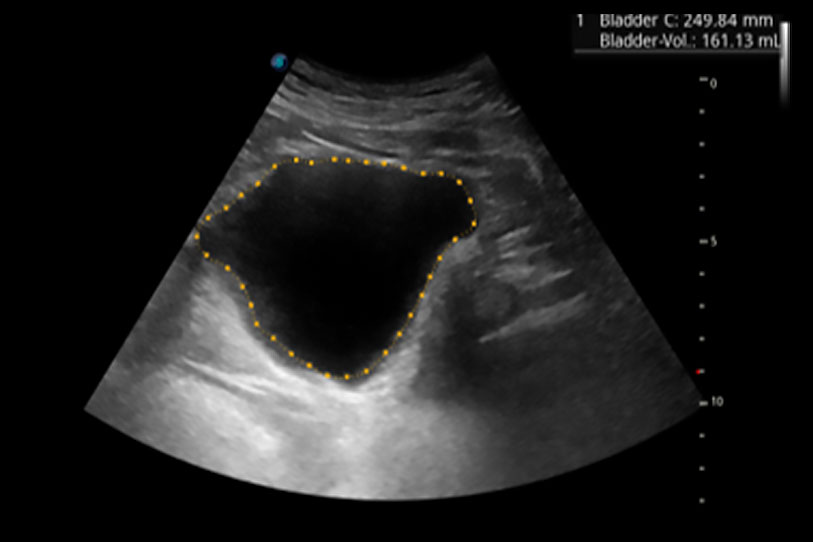

一键自动识别膀胱壁及自动测量膀胱容积,不受膀胱形状和大小的限制,帮助医生快速精准获得测量的数据。